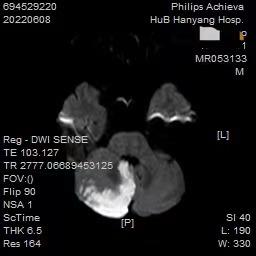

病例A :25岁的年轻人,头晕1周,前来就诊。起病后自行在网上查,觉得就是没休息好,后来又发现像“颈椎病”,觉得自己年轻,调整一下就恢复了。结果1周了,还是晕,上网搜“是不是脑梗中风?”,心里开始发紧了。赶紧到医院指挥医生,“别问这多的,那些检查我都不做,我要做核磁,我要排除脑梗”。头部核磁结果出来了,“正常的,没有急性中风病灶”,说什么都不愿继续检查和治疗了,“我要去做理疗”。1周后患者再次来到诊室,“医生我晕还没有好,睡眠也不太好,晕也不想去参加活动……”,瞬间有点emo了,病人逐渐变成慢性头晕影响生活质量了。 病例B :67岁老年人,有高血压病史,头晕、眩晕1周就诊。一开始起病后症状不重,患者自认为“眩晕症发了”,*毛老**病,扛一扛,自己吃点眩晕的药就会好的。结果症状逐渐加重,开始出现走路不稳、右边手脚麻木,前来求治。头部核磁共振提示右侧小脑半球急性脑梗死,头颈部动脉硬化改变,右侧椎动脉闭塞(见下图),但急性期溶栓时间已过。